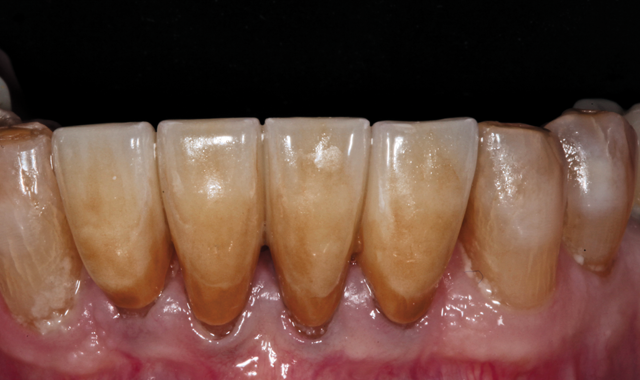

An 88-year-old man presented for restoration of tooth #25, which was fractured and had been endodontically treated (Fig. 1). A thorough intraoral and radiographic examination was performed, which revealed damage to the remaining anterior mandibular teeth incurred over the years as a result of scaling and curettage (Fig. 2). This damage to the

Fig. 2

root surface of the lower incisors-which was visible on the radiograph (Fig. 3)-is known as “Riffle-ization.” Described by Dr. Riffle as a technique for removing every last bit of calculus during repeated root scaling, what is now known as “Riffle-izing," ultimately-over the years-changes the shape of the neck of the tooth to resemble an hour glass.

Therefore, based on the clinical and visual evaluation, the preferred treatment would be to restore the fractured #25 with a post and crown and four splinted crowns to restore the anatomy of the four incisors and increase their resistance to both mobility and fracture.